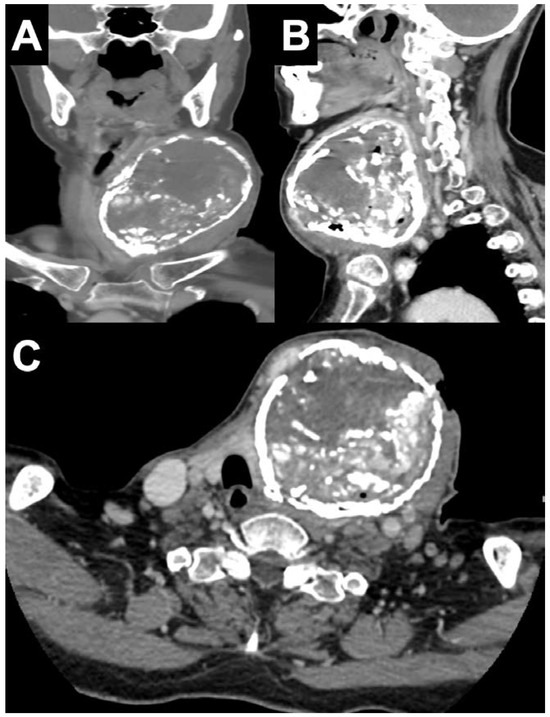

Introduction: Acute suppurative thyroiditis (AST) is an uncommon but potentially life-threatening condition. The majority of AST cases are caused by bacterial infection. Streptococcus suis is a swine pathogen that mostly causes meningitis and septice...